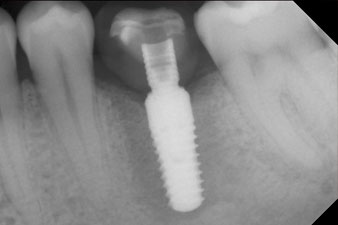

x-ray check

Fig. 10: The x-ray check shows the success of the osseointegration and the crown screwed in position without a gap.